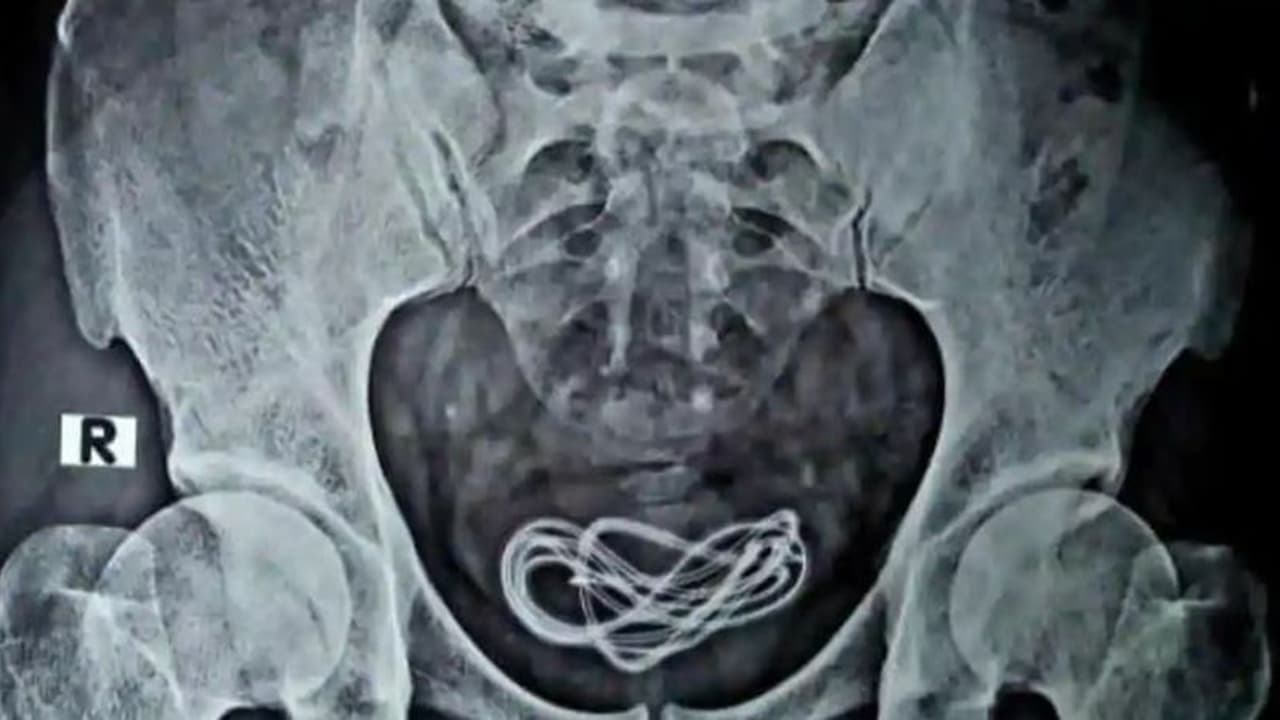

ഓപ്പറേഷൻ ടേബിളിൽ എക്സ്-റേ പരിശോധന നടത്തിയപ്പോൾ യുവാവിന്റെ മൂത്രസഞ്ചിയിലാണ് കേബിൾ ഉള്ളതെന്ന് കണ്ടെത്തി. ഓപ്പറേഷനിലൂടെ കേബിൾ നീക്കുകയും ചെയ്തു. യുവാവ് ഇപ്പോൾ സുഖംപ്രാപിച്ച് വരികയാണെന്നും ഡോക്ടർ പറഞ്ഞു.